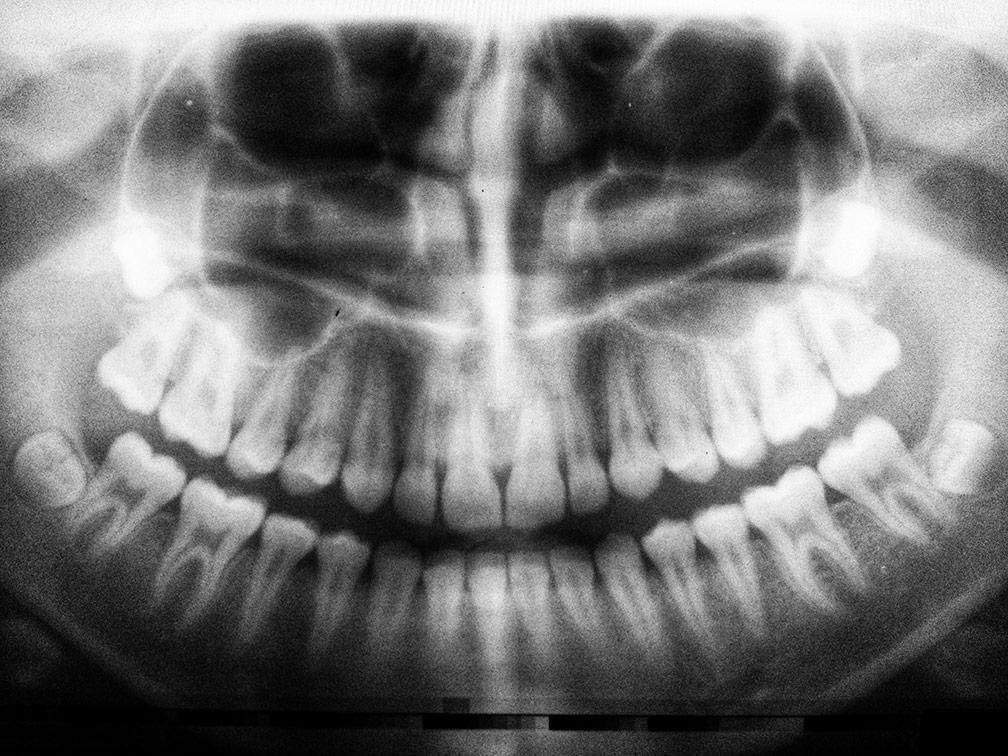

It’s interesting to note that according to some estimates, up to 25% of Americans don’t have wisdom teeth at all. Dental x-rays, taken at a checkup during your teen years can see if you’re one of the lucky few.